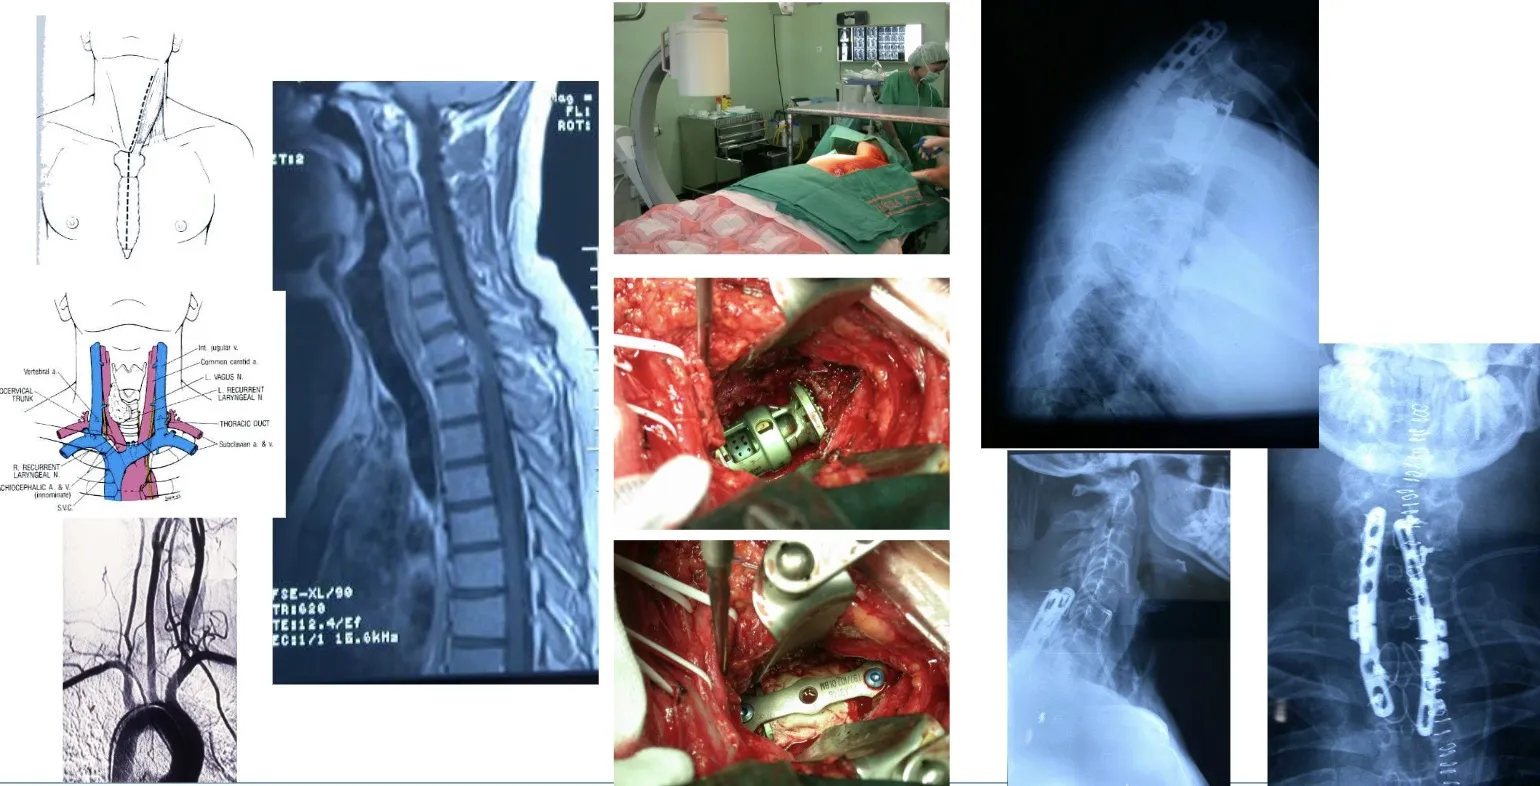

La técnica neuroquirúrgica ha avanzado de forma notable en los últimos años, hasta el punto de que hoy es posible abordar toda la columna vertebral, desde la base del cráneo (a través de la boca) hasta el sacro, mediante vías anterior, posterior o lateral, según la localización y la naturaleza del tumor. En la actualidad, prácticamente no existe ninguna zona de la columna que no pueda abordarse quirúrgicamente con seguridad y precisión, gracias a estos progresos técnicos y tecnológicos.

En la figura se muestra un ejemplo de abordaje transoral, es decir, realizado a través de la boca, para acceder a un tumor localizado en la segunda vértebra cervical. Este tipo de intervención permite alcanzar directamente la lesión situada en la parte anterior de la columna cervical alta, garantizando un acceso preciso y un control adecuado del campo quirúrgico.

En estos casos, es posible utilizar sistemas de fijación que permiten anclar el cráneo a la columna cervical, con el fin de mantener la estabilidad y evitar el colapso producido por la invasión tumoral de la vértebra afectada. Estas fijaciones, realizadas mediante placas, tornillos y barras especialmente diseñadas, aseguran la continuidad estructural entre el cráneo y la columna, garantizando la correcta alineación y protección de las estructuras neurológicas.

También es posible acceder a la columna cervical por vía anterior y resecar una vértebra completa cuando la lesión lo requiere. Este abordaje permite eliminar totalmente el cuerpo vertebral afectado, descomprimir la médula espinal y, posteriormente, reconstruir y estabilizar la zona mediante injertos óseos o dispositivos protésicos que restituyen la alineación y la función de la columna.

Otra opción es acceder por vía posterior, lo que permite realizar una fijación más sólida y estable mediante la colocación de tornillos y barras en los elementos posteriores de la columna. Este tipo de abordaje ofrece un mayor refuerzo estructural, especialmente útil cuando existe pérdida de sostén anterior o es necesario complementar una reconstrucción realizada previamente por vía anterior.

Incluso las transiciones vertebrales —zonas especialmente complejas desde el punto de vista anatómico—, como la unión cervicotorácica, presentan grandes desafíos quirúrgicos. En esta región, la presencia del esternón dificulta el acceso directo, por lo que en determinados casos es necesaria la colaboración con cirujanos cardiovasculares. Esto permite trabajar con seguridad entre las ramas principales de la aorta y las arterias que irrigan el cerebro, garantizando un abordaje controlado y minimizando los riesgos durante la intervención.